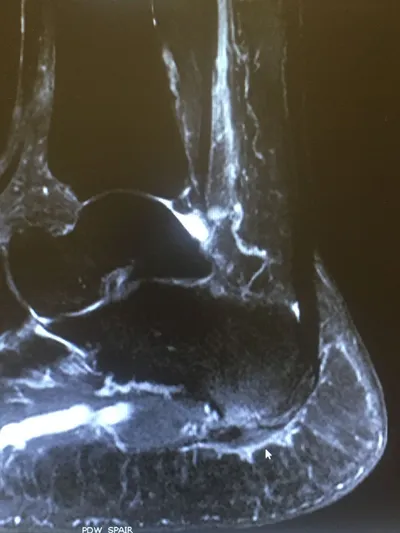

MRI of Severe Plantar Fasciitis of the Medial and Central Band. The bands of the plantar fascia are thickened and there is swelling around the soft tissue of where the fascia inserts in the heel as well in the heel bone itself. On this MRI, the white is inflammation.The arrow points to the thickend and inflammed ligament.